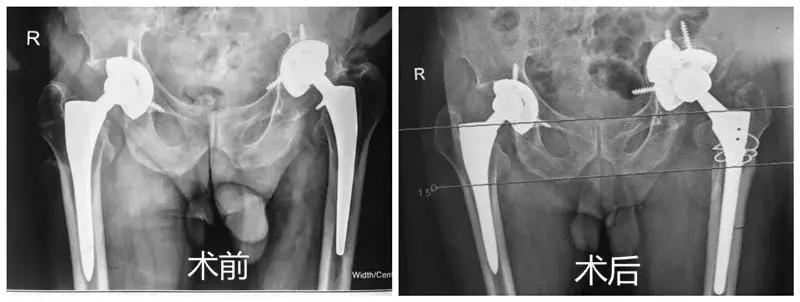

最后,关节外科专家们想到了3D打印技术,先通过CT扫描获得林嗲嗲髋臼缺损的三维数据,再用3D打印技术制作出和他患侧髋臼一模一样的实体模型供术前计划参考,同时定制出适合髋臼缺损形态的钛合金金属垫块联合多孔钛合金臼杯完成翻修。

完善术前准备后,林嗲嗲被推进手术室,由刘荆陵主任主刀,其他经验丰富的医生协助,小心翼翼地先把松动假体取出,术中发现骨缺损区大小形态和3D打印的模型一模一样,按照术前设计,安装定制的钛合金金属垫块和多孔钛合金臼杯,最终完成关节翻修。术后半个月,林嗲嗲是走着出院回家的。